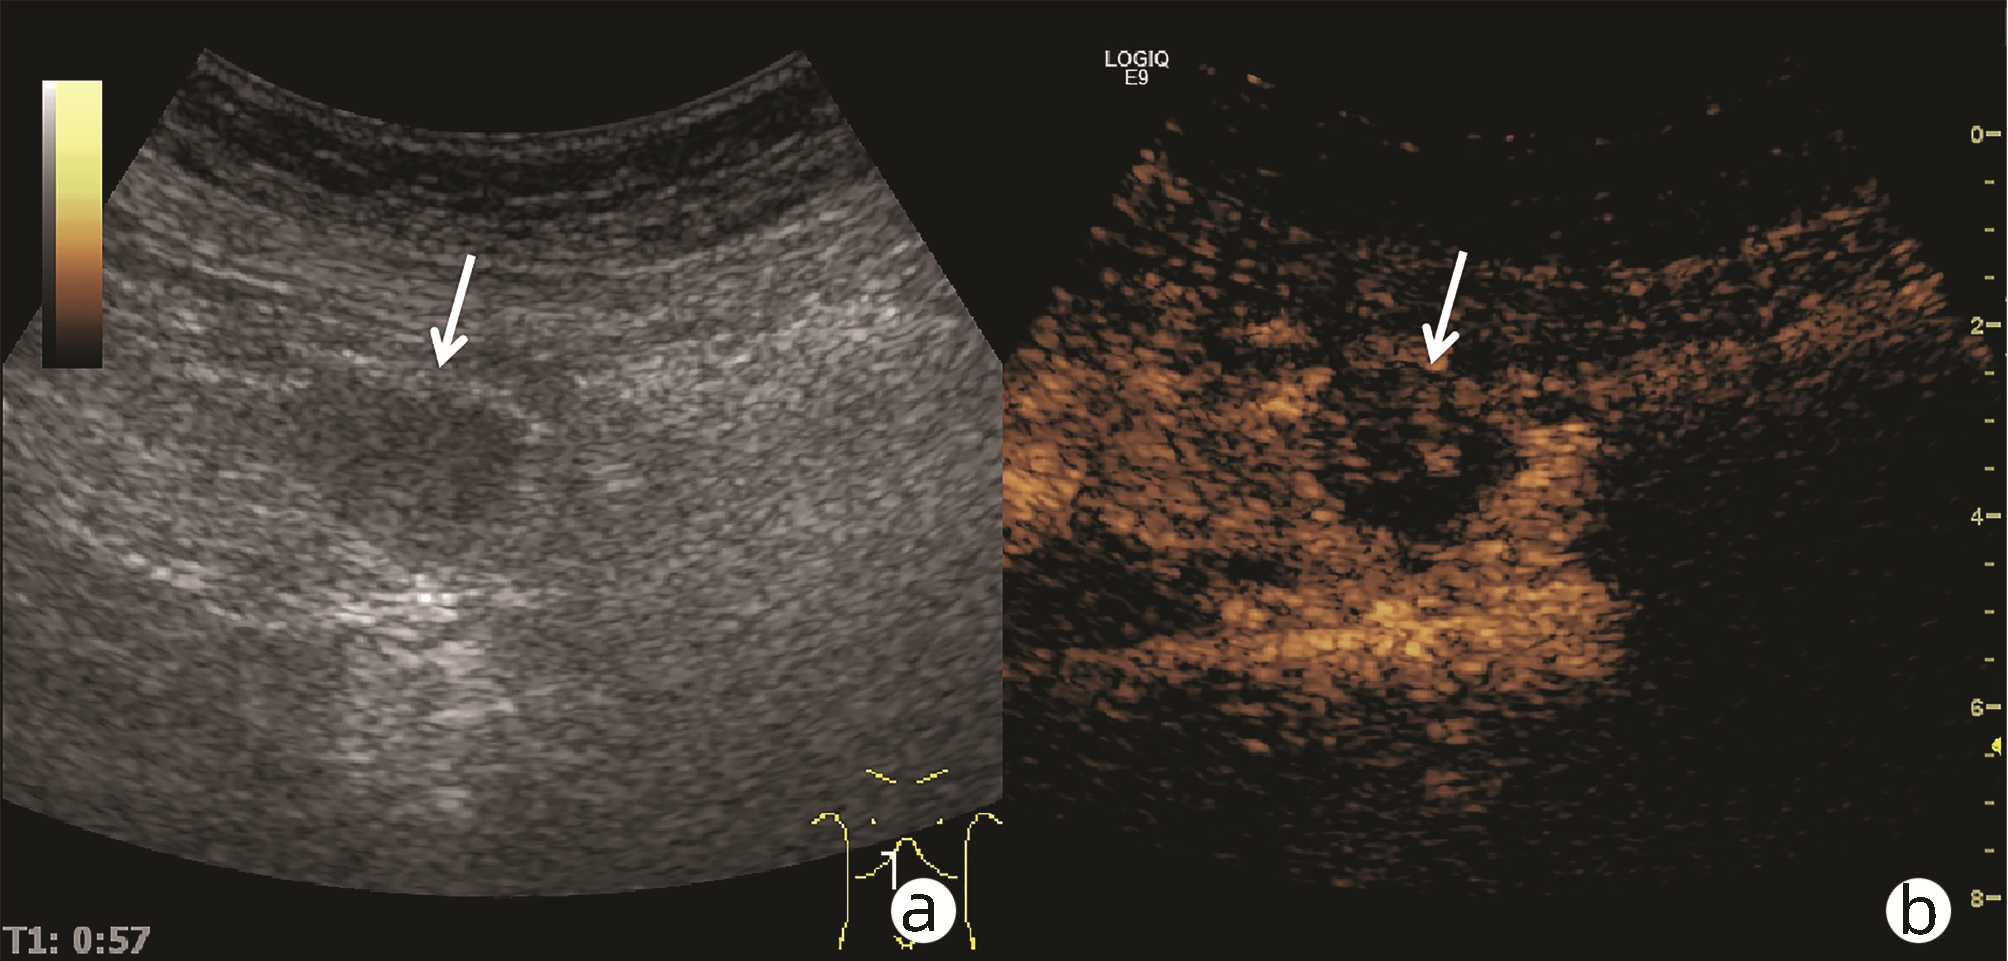

•   Objective  To investigate the value of ultrasound and contrast-enhanced ultrasound (CEUS) in the differential diagnosis of mass-type autoimmune pancreatitis (AIP) and pancreatic ductal adenocarcinoma (PDAC).  Methods  A retrospective analysis was performed for the clinical data, ultrasound findings, and CEUS findings of 11 patients with mass-type AIP who were diagnosed in Tangshan Workers' Hospital from January 2015 to December 2020, and their characteristic manifestations were analyzed and compared with the data of 23 patients with PDCA. The chi-square test was used for comparison of categorical data between two groups.  Results  For the 11 patients with mass-type AIP, CEUS had a diagnostic accuracy of 63.64%, and all of these patients had hypoechoic single lesions; the patients with clear boundaries, regular morphology, pancreatic duct dilatation or cutoff, and blood flow signal accounted for 54.55%, 63.64%, 18.18%, and 36.36%, respectively, while in the PDCA group, such patients accounted for 30.43%, 34.78%, 78.26%, and 21.74%, respectively, and there was a significant difference in the presence or absence of pancreatic duct dilatation or cutoff between the two groups(χ2=11.089, P < 0.05), with no significant differences in the other indices (all P > 0.05). For the 11 patients with mass-type AIP, CEUS showed that 7 patients (63.64%) had hyperenhancement and 4 (36.36%) had iso-enhancement in the arterial phase, and 5 patients (45.45%) had hyperenhancement in the arterial phase and 6 (54.55%) had iso-enhancement in the venous phase; for the 23 patients with PDCA, 22 (95.65%) had hypoenhancement of lesions in both arterial and venous phases, and there were significant differences in the enhancement pattern in arterial and venous phases between the two groups (χ2=30.345 and 30.084, both P < 0.05).  Conclusion  The enhancement pattern of CEUS and the presence or absence of pancreatic duct dilatation or cutoff have a relatively high value in the differential diagnosis of mass-type AIP and PDCA.